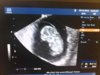

a ja na to , ze jak nie będzie. Ze po to przyszłam żeby mnie zbadał, chce się upewnić cokolwiek...dobra z łaską zrobił mi USG no i uff widac pęcherzyk na swoim miejscu czyli w macicy (i tu mi ulżyło) ...no i to wszystko. NIe zmierzył go ani nic więcej. Więcej nic nie wiem...Kazał brać kwas foliowy i robić to co do tej pory.... ejjjjj Nie zlecił badań, nie powiedział nic więcej i zbył mnie nie odpowiadając na moje pytania...